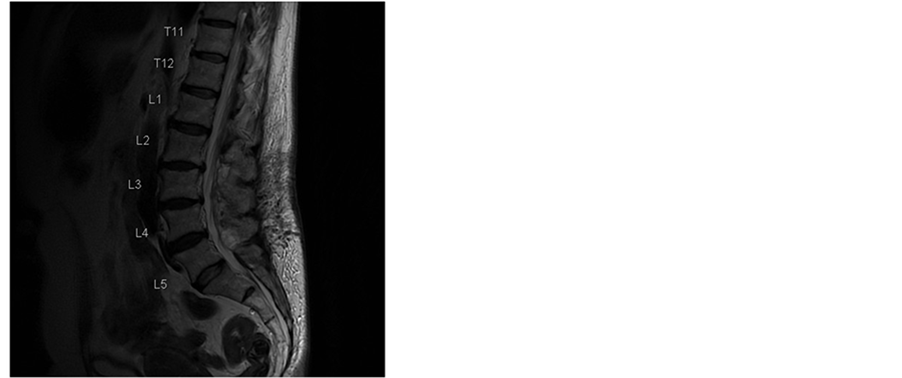

In the next weeks our patient recovered slowly. MRIs were performed and showed a slow reabsorption of the haematoma (Figure 2 and Figure 3). Clinically at the 3-month control the patient had no neurological signs or symptoms (such as radicular pain, neuropathic pain or paresthesia) and no signs of polyradiculo(neuro)pathy.

Figure 2. T2-weighted MR images of the lumbar spine in sagittal and axial planes 3 weeks after surgery. There is considerable regression of the epidural hematoma.